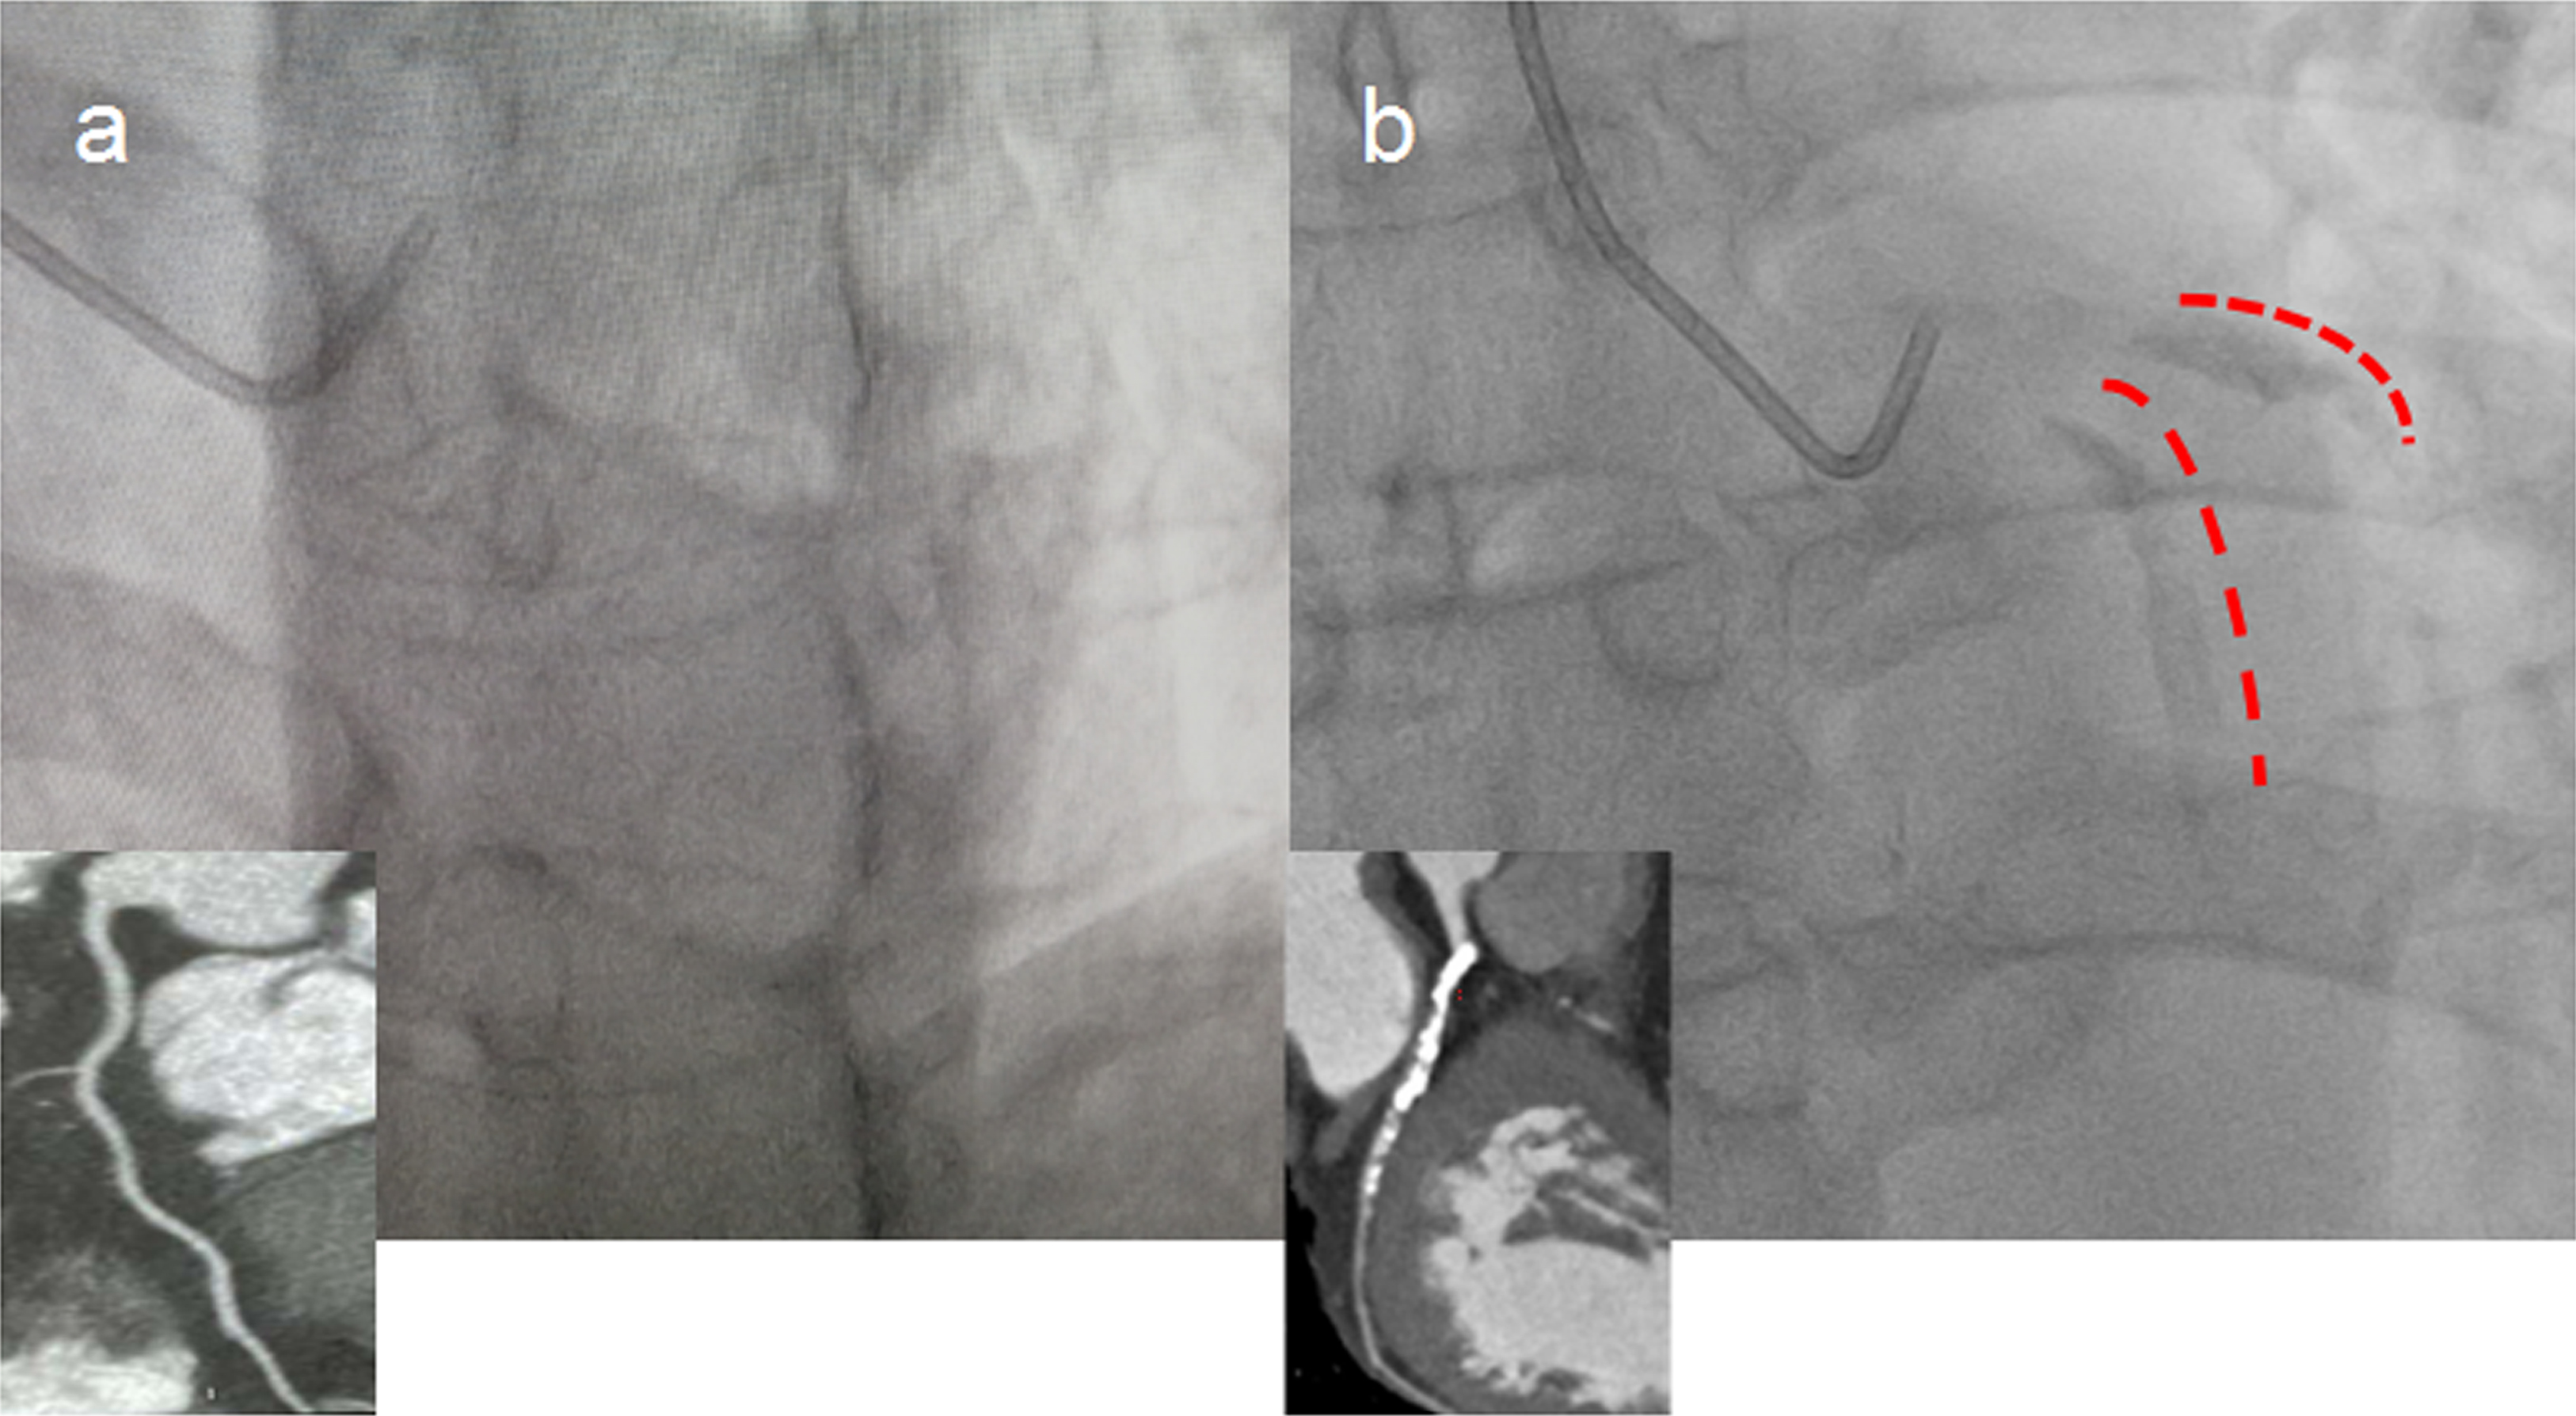

Patients in this study were from our prospective registration study, in which patients with severe calcified coronary lesions on angiographic images who underwent percutaneous coronary intervention (PCI) with orbital atherectomy were recruited between February 2020 and May 2021 (registered on the Chinese Clinical Trial Registry [ChiCTR] 2000029775). Severe calcified coronary lesions were defined as the presence of apparent radiative opacities within the coronary lumen [10]. Based on qualitative visual assessment of calcified lesions using fluoroscopy, they were classified as severe (radio-opacities located on both sides of the coronary arterial wall before contrast injection and without cardiac movement), moderate (densities were acquired during the cardiac cycle before contrast injection), or none/mild calcified lesions according to the published literature [11]. An example of severe calcified coronary lesions on angiographic images is given in Fig. 1. Two cardiologists who were unaware of the patients included in this study assessed the angiographic calcification. Some cases of disagreement were adjudicated by a third independent cardiologist and given the final diagnosis. The recruited control subjects were matched by age, sex, and conventional risk factors. The control subjects were selected during the same period in the same hospital with non-calcific coronary angiography findings. Subjects with a known history of malignant tumors, serious system diseases, severe respiratory disease, renal or hepatic insufficiency, and acute infections were not included. The clinical and demographic information of the participants was recorded. The study protocol was approved by our institutional ethics committee, and written informed consent was obtained from all patients. The study was designed in accordance with the ethical guidelines of the Declaration of Helsinki.

Fig. 1.Representative image of severe calcified coronary lesions detected by coronary angiography. (a) Controls without coronary artery calcification (non-CAC). (b) Patients with coronary artery calcification (CAC). Red marks indicate severe calcified left anterior descending artery (LAD) lesions detected by x-ray and the corresponding image from coronary computed tomography angiography (CTA).